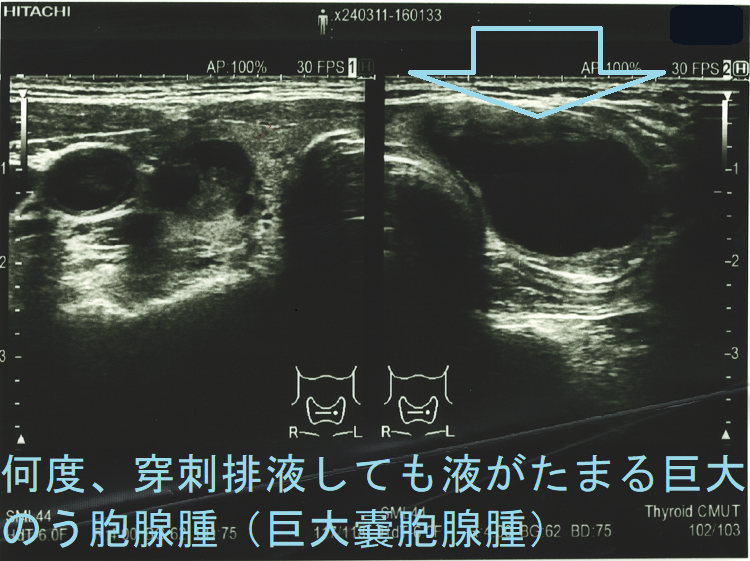

甲状腺癌と確定できない、または癌ではない甲状腺腫瘍の手術適応は①4cm以上(相対的適応)②増大傾向(甲状腺癌を否定できない、増大傾向の腺腫様甲状腺腫は約3%、濾胞性腫瘍は約18%が癌)③血中サイログロブリン値1000ng/mL以上(甲状腺癌を否定できない、甲状腺乳頭癌では有用性なく甲状腺乳頭癌を除くと46%が甲状腺濾胞癌)④超音波エコー検査・細胞診で甲状腺癌を完全に否定できない⑤気管食道などを圧迫、息しにくい、飲み込みにくい⑥縦隔内進展⑦美容上の問題(首が腫れている)⑧何度、穿刺排液しても液がたまる巨大のう胞腺腫(巨大嚢胞腺腫)。

- (良性)のう胞腺腫(嚢胞腺腫)[単に、のう胞(嚢胞)と呼ばれる事が多い]で、気管食道などを圧迫し、息がしにくい・飲み込みにくいなどに加え、穿刺排液困難や何度、穿刺排液してもすぐに液がたまる巨大のう胞腺腫(巨大嚢胞腺腫)

頻回に穿刺排液しても液がたまる巨大のう胞腺腫(巨大嚢胞腺腫)は、良性腫瘍(のう胞型濾胞腺腫:嚢胞型濾胞腺腫)であっても手術適応になります。単に、のう胞(嚢胞)と呼ばれる事も多いですが、甲状腺組織の破壊・変性によるのう胞変性(嚢胞変性)でなく、れっきとした腫瘍です。

頻回に穿刺排液しても、

なら、内分泌外科に甲状腺部分切除(半葉切除が多い)を依頼します。

岩手県立中央病院の報告;97 x 71 x 60 mmの巨大な甲状腺のう胞腺腫(甲状腺嚢胞腺腫)で、排液後1週間以内に液が再貯留し始めたため、甲状腺半葉切除したそです。病理標本では、のう胞周囲は炎症が強く、炎症性浸出液の可能性が考えられます。(第57回 日本甲状腺学会 P2-070 巨大な甲状腺嚢胞により経口摂取困難となった一例)

ケース① 巨大のう胞腺腫(巨大嚢胞腺腫) 7 cm以上